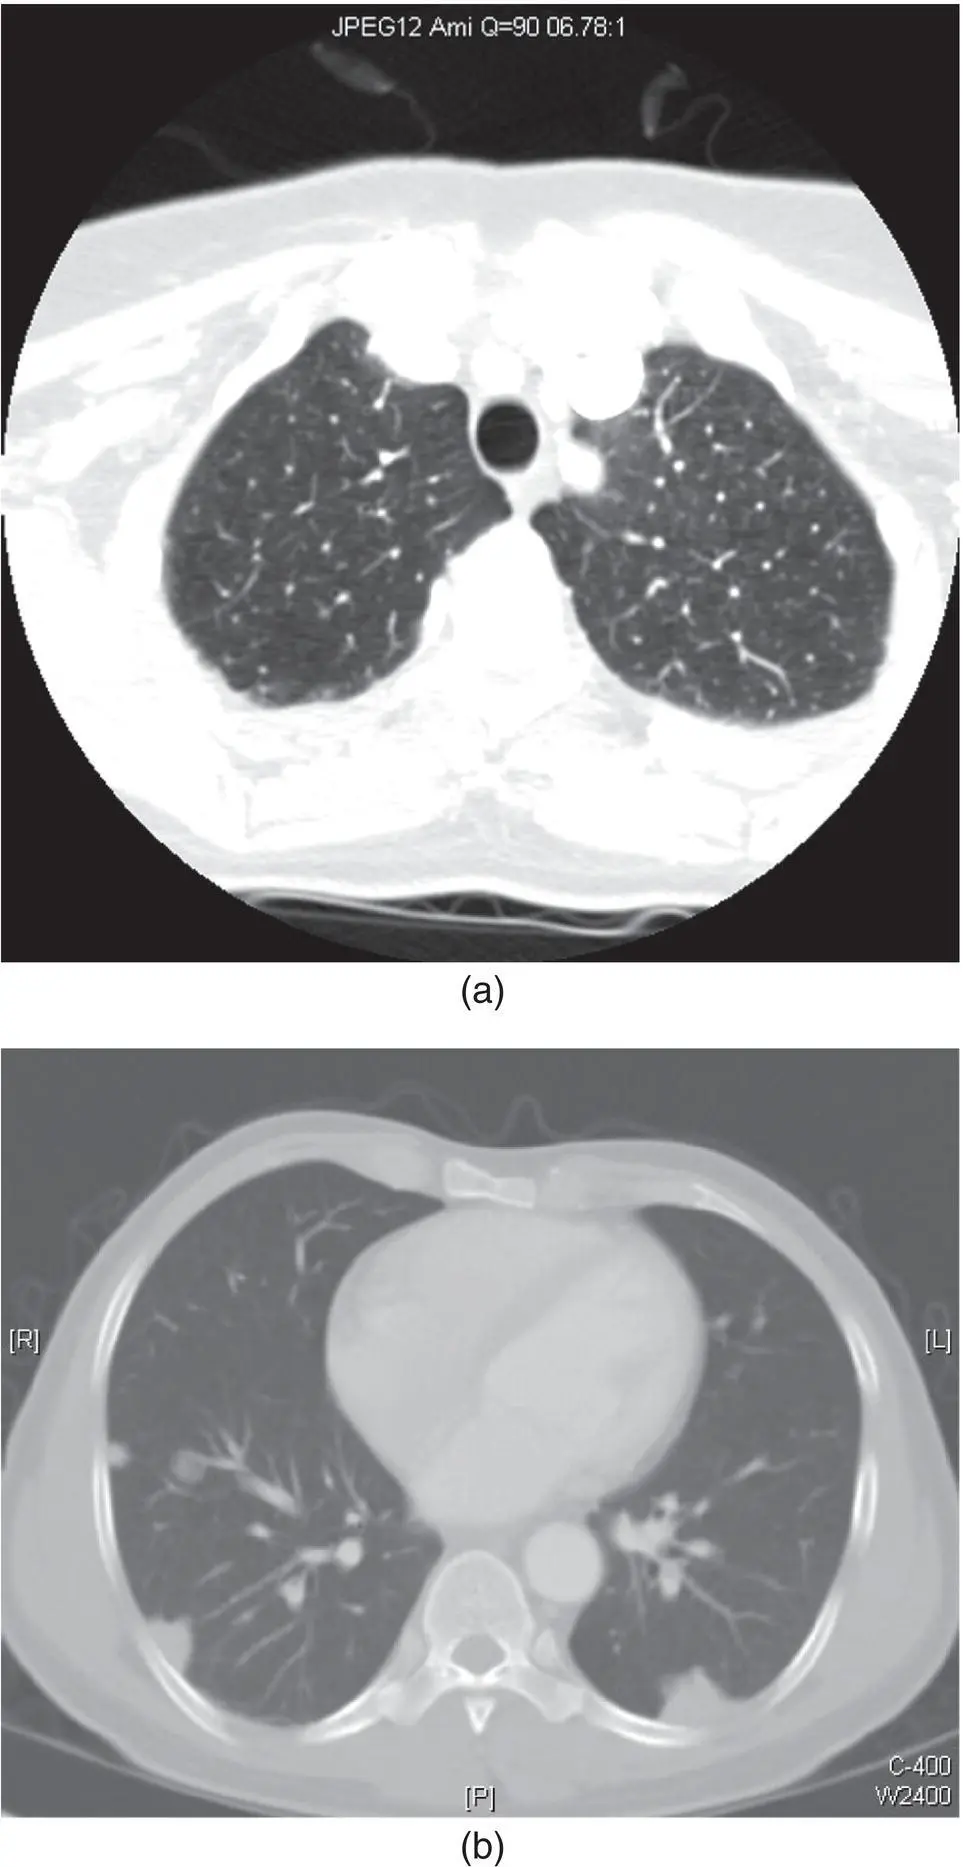

Figure 2.4. Axial CT of the neck at the thoracic inlet in lung windows demonstrating lung parenchyma (a). Axial image of dedicated CT of chest demonstrating cannon ball lesions in a patient previously treated for adenoid cystic carcinoma of the palate (b). These lesions are representative of diffuse metastatic disease of the lungs, but not pathognomonic of adenoid cystic carcinoma.